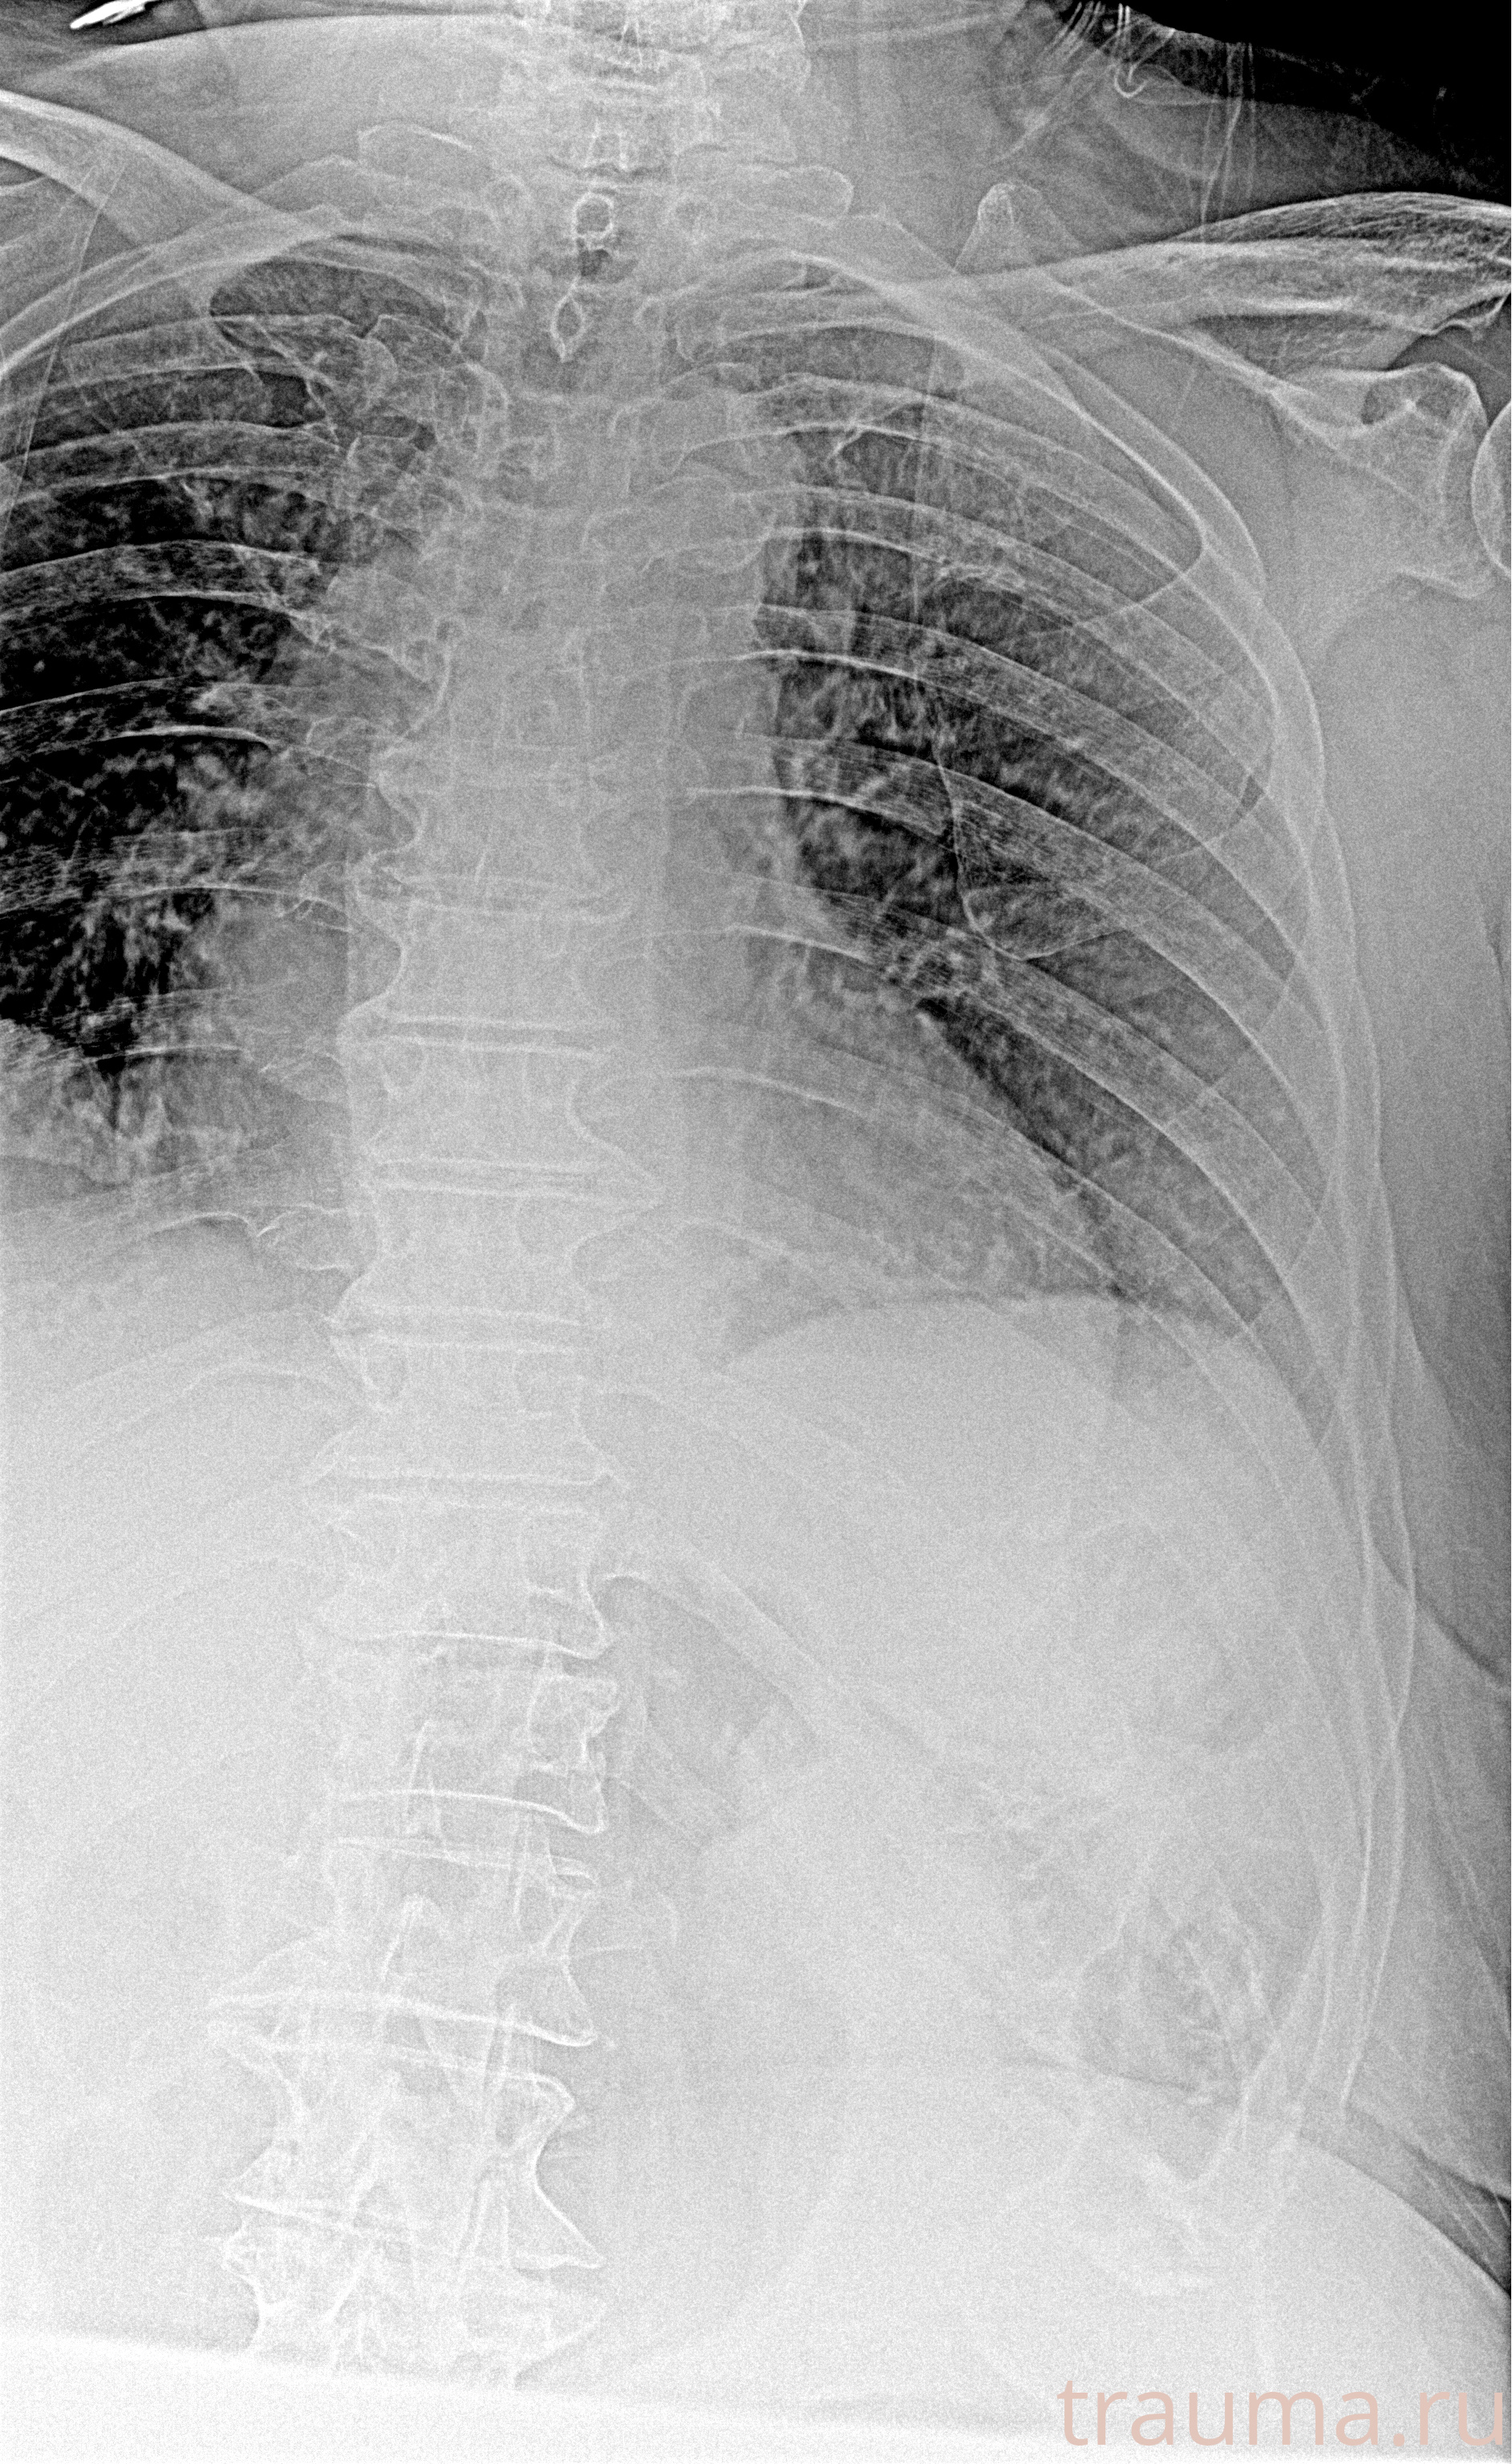

Рентгенограммы

Рентген на дому: по вашему адресу приезжает врач-рентгенолог, травматолог-ортопед с мобильным рентгеновским аппаратом, проводит диагностику травмы или заболевания, делает необходимые рентгенограммы, дает рекомендации по дальнейшему лечению. Получить качественные снимки в домашних условиях возможно благодаря уникальной методике, разработанной МосРентген Центром для института  Склифосовского

при переломе шейки бедра и пневмонии от компании МосРентген Центр - партнера Института имени Склифосовского